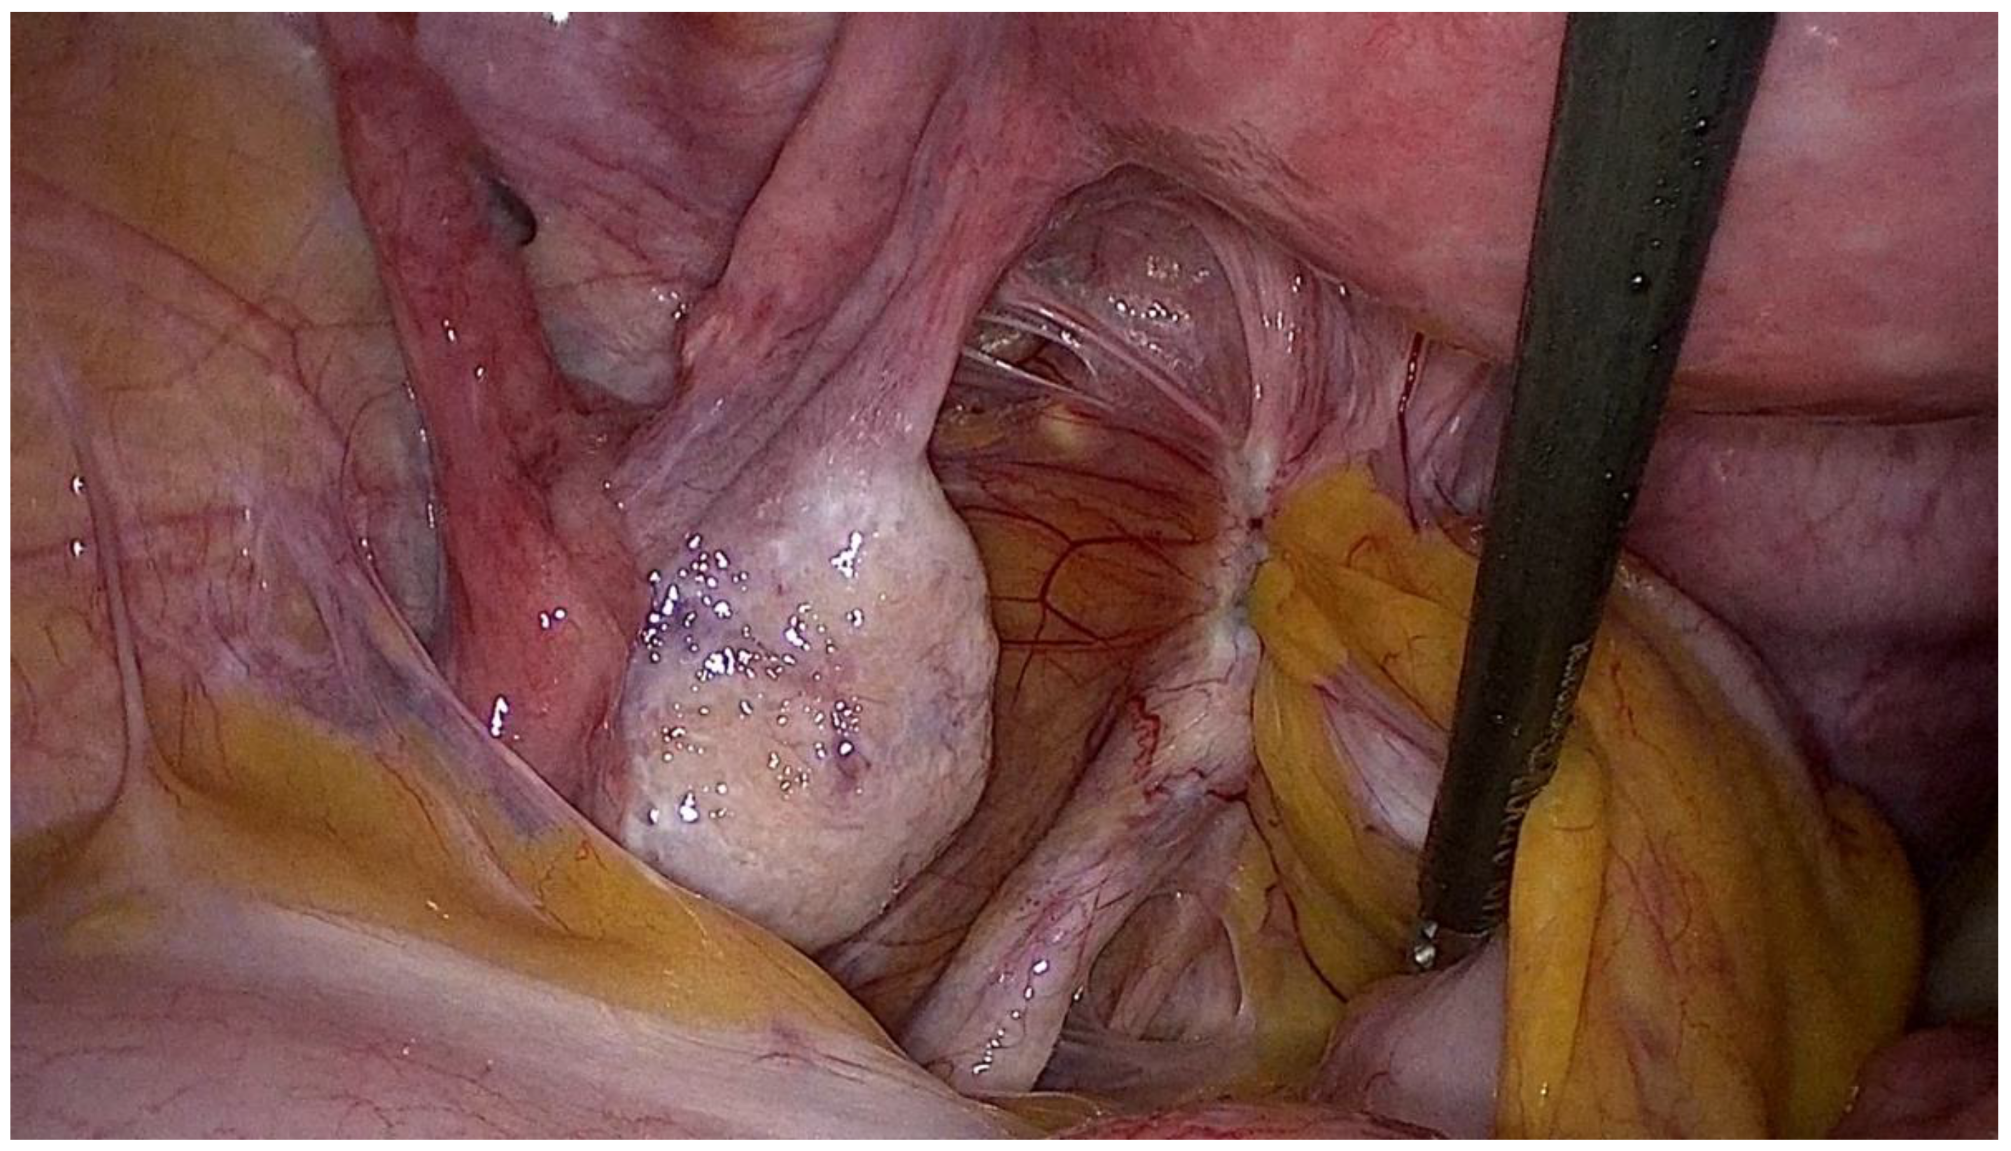

Figure 3.

Laparoscopic view of endometriosis of the posterior compartment involving the left uterosacral ligament and the rectum.